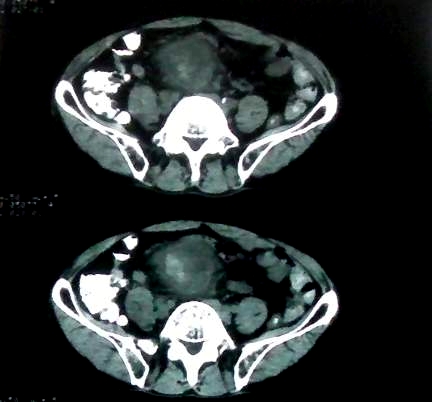

男 60岁,下腹部肿块半年余

前列腺肥大,密度不均。伴盆腔实性肿块。考虑前列腺癌伴盆腔转移。建议增强扫描。

考虑来源于肠道的肿瘤,乙状结肠?询问排便情况

盆腔恶性占位,间质瘤可能性大

乙状结肠间质瘤

盆腔恶性占位,间质瘤可能性大。

考虑盆腔内间质瘤可能性大。

病理结果:肠系膜肉瘤

肠系膜的原发性肠系膜肿瘤比较少见,大体可分为囊性和实性两类。囊性肿瘤多为良性。实性肿瘤可以为良性和恶性,恶性肿瘤以恶性淋巴瘤为最多,其次是脂肪肉瘤、平滑肌肉瘤、纤维肉瘤等。恶性肿瘤约占实体肿瘤的6% [1] 。文献资料显示原发性肠系膜肿瘤约7%位于小肠系膜,其中60%位于回肠系膜和肠系膜根部,结肠系膜和阑尾系膜仅占20%左右 [2] 。由于肠系膜肿瘤在临床上不多见,症状无特异性,起病隐匿,早期可无症状,只有当肿瘤增大压迫周围的组织脏器时,才有可能出现相应的症状,并且这些症状常与邻近器官受压有关。腹部包块是主要的症状,临床表现为发热、乏力、腹部隐痛不适和饱胀感、消瘦,偶有呕吐及便秘,当肿瘤出血和囊肿突然增大时,可有腹痛,压迫症状有肠梗阻,下肢肿胀,肾盂积水等表现。体格检查时可触及腹部肿块,且活动度好,尤其是横向移动。b超可早期发现腹块,并可确定大小、性质及部位。x线钡剂灌肠检查,虽然不能提供系膜肿瘤的直接诊断依据,可显示为与肠管关系密切之外在性肿物,并可排除肠管、泌尿系等疾病[3] 。腹腔镜对原因不明的腹痛及性质不明的腹块,既可定性又可定位,其正确诊断率为74% [4] 。肠系膜良性肿瘤和恶性肿瘤的病程长短进行比较,恶性肿瘤绝大多数病程均在半年以内,没有超过2年以上。良性肿瘤大多数病程均在2年以上。这一点在诊断上具有鉴别意义。

病灶形态不规则,偏心性裂隙样坏死,支持恶性病变。来源不好定。感谢反馈结果--肠系膜肉瘤。